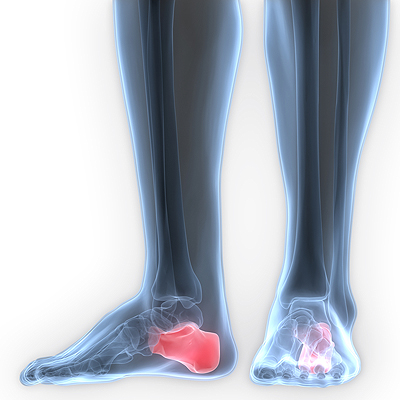

When pressure is put on the joint of the big toe over a period of time, the foot condition referred to as a bunion may develop. This condition, or foot deformity, appears as a bump on the side of the big toe. One of the most common causes of this deformity is ill-fitting or tightly worn footwear. Existing conditions may also factor into the development of a bunion. Flat feet, gout, injury to the foot, and connective tissue or neuromuscular disorders may all increase the risk of developing a bunion. Bunions can be rather painful, often causing discomfort when wearing shoes or walking. This condition can also cause the big toe to feel numb, as well become red and inflamed. For more information on how to treat a bunion, please speak with a podiatrist for professional advice.

When pressure is put on the joint of the big toe over a period of time, the foot condition referred to as a bunion may develop. This condition, or foot deformity, appears as a bump on the side of the big toe. One of the most common causes of this deformity is ill-fitting or tightly worn footwear. Existing conditions may also factor into the development of a bunion. Flat feet, gout, injury to the foot, and connective tissue or neuromuscular disorders may all increase the risk of developing a bunion. Bunions can be rather painful, often causing discomfort when wearing shoes or walking. This condition can also cause the big toe to feel numb, as well become red and inflamed. For more information on how to treat a bunion, please speak with a podiatrist for professional advice.

A bunion is formed of swollen tissue or an enlargement of boney growth, usually located at the base joint of the toe that connects to the foot. The swelling occurs due to the bones in the big toe shifting inward, which impacts the other toes of the foot. This causes the area around the base of the big toe to become inflamed and painful.

Podiatrists often perform two tests – blood tests and x-rays – when trying to diagnose bunions, especially in the early stages of development. Blood tests help determine if the foot pain is being caused by something else, such as arthritis, while x-rays provide a clear picture of your bone structure to your provider.

A bunion is an enlargement of the base joint of the toe that connects to the foot, often formed from a bony growth or a patch of swollen tissues. It is caused by the inward shifting of the bones in the big toe, toward the other toes of the foot. This shift can cause a serious amount of pain and discomfort. The area around the big toe can become inflamed, red, and painful.

Bunions are most commonly formed in people who are already genetically predisposed to them or other kinds of bone displacements. Existing bunions can be worsened by wearing improperly fitting shoes. Trying to cram your feet into high heels or running or walking in a way that causes too much stress on the feet can exacerbate bunion development. High heels not only push the big toe inward, but shift one's body weight and center of gravity towards the edge of the feet and toes, expediting bone displacement.

A podiatrist knowledgeable in foot structure and biomechanics will be able to quickly diagnose bunions. Bunions must be distinguished from gout or arthritic conditions, so blood tests may be necessary. The podiatrist may order a radiological exam to provide an image of the bone structure. If the x-ray demonstrates an enlargement of the joint near the base of the toe and a shifting toward the smaller toes, this is indicative of a bunion.

Wearing wider shoes can reduce pressure on the bunion and minimize pain, and high heeled shoes should be eliminated for a period of time. This may be enough to eliminate the pain associated with bunions; however, if pain persists, anti-inflammatory drugs may be prescribed. Severe pain may require an injection of steroids near the bunion. Orthotics for shoes may be prescribed which, by altering the pressure on the foot, can be helpful in reducing pain. These do not correct the problem; but by eliminating the pain, they can provide relief.

For cases that do not respond to these methods of treatment, surgery can be done to reposition the toe. A surgeon may do this by taking out a section of bone or by rearranging the ligaments and tendons in the toe to help keep it properly aligned. It may be necessary even after surgery to wear more comfortable shoes that avoid placing pressure on the toe, as the big toe may move back to its former orientation toward the smaller toes.